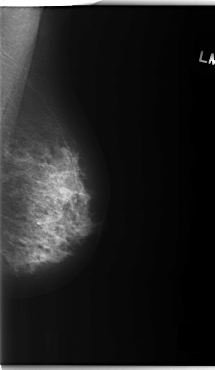

C_0232_1.LEFT_MLO

LEFT_MLO LINES 5912 PIXELS_PER_LINE 3440 BITS_PER_PIXEL 12 RESOLUTION 50 NON_OVERLAY